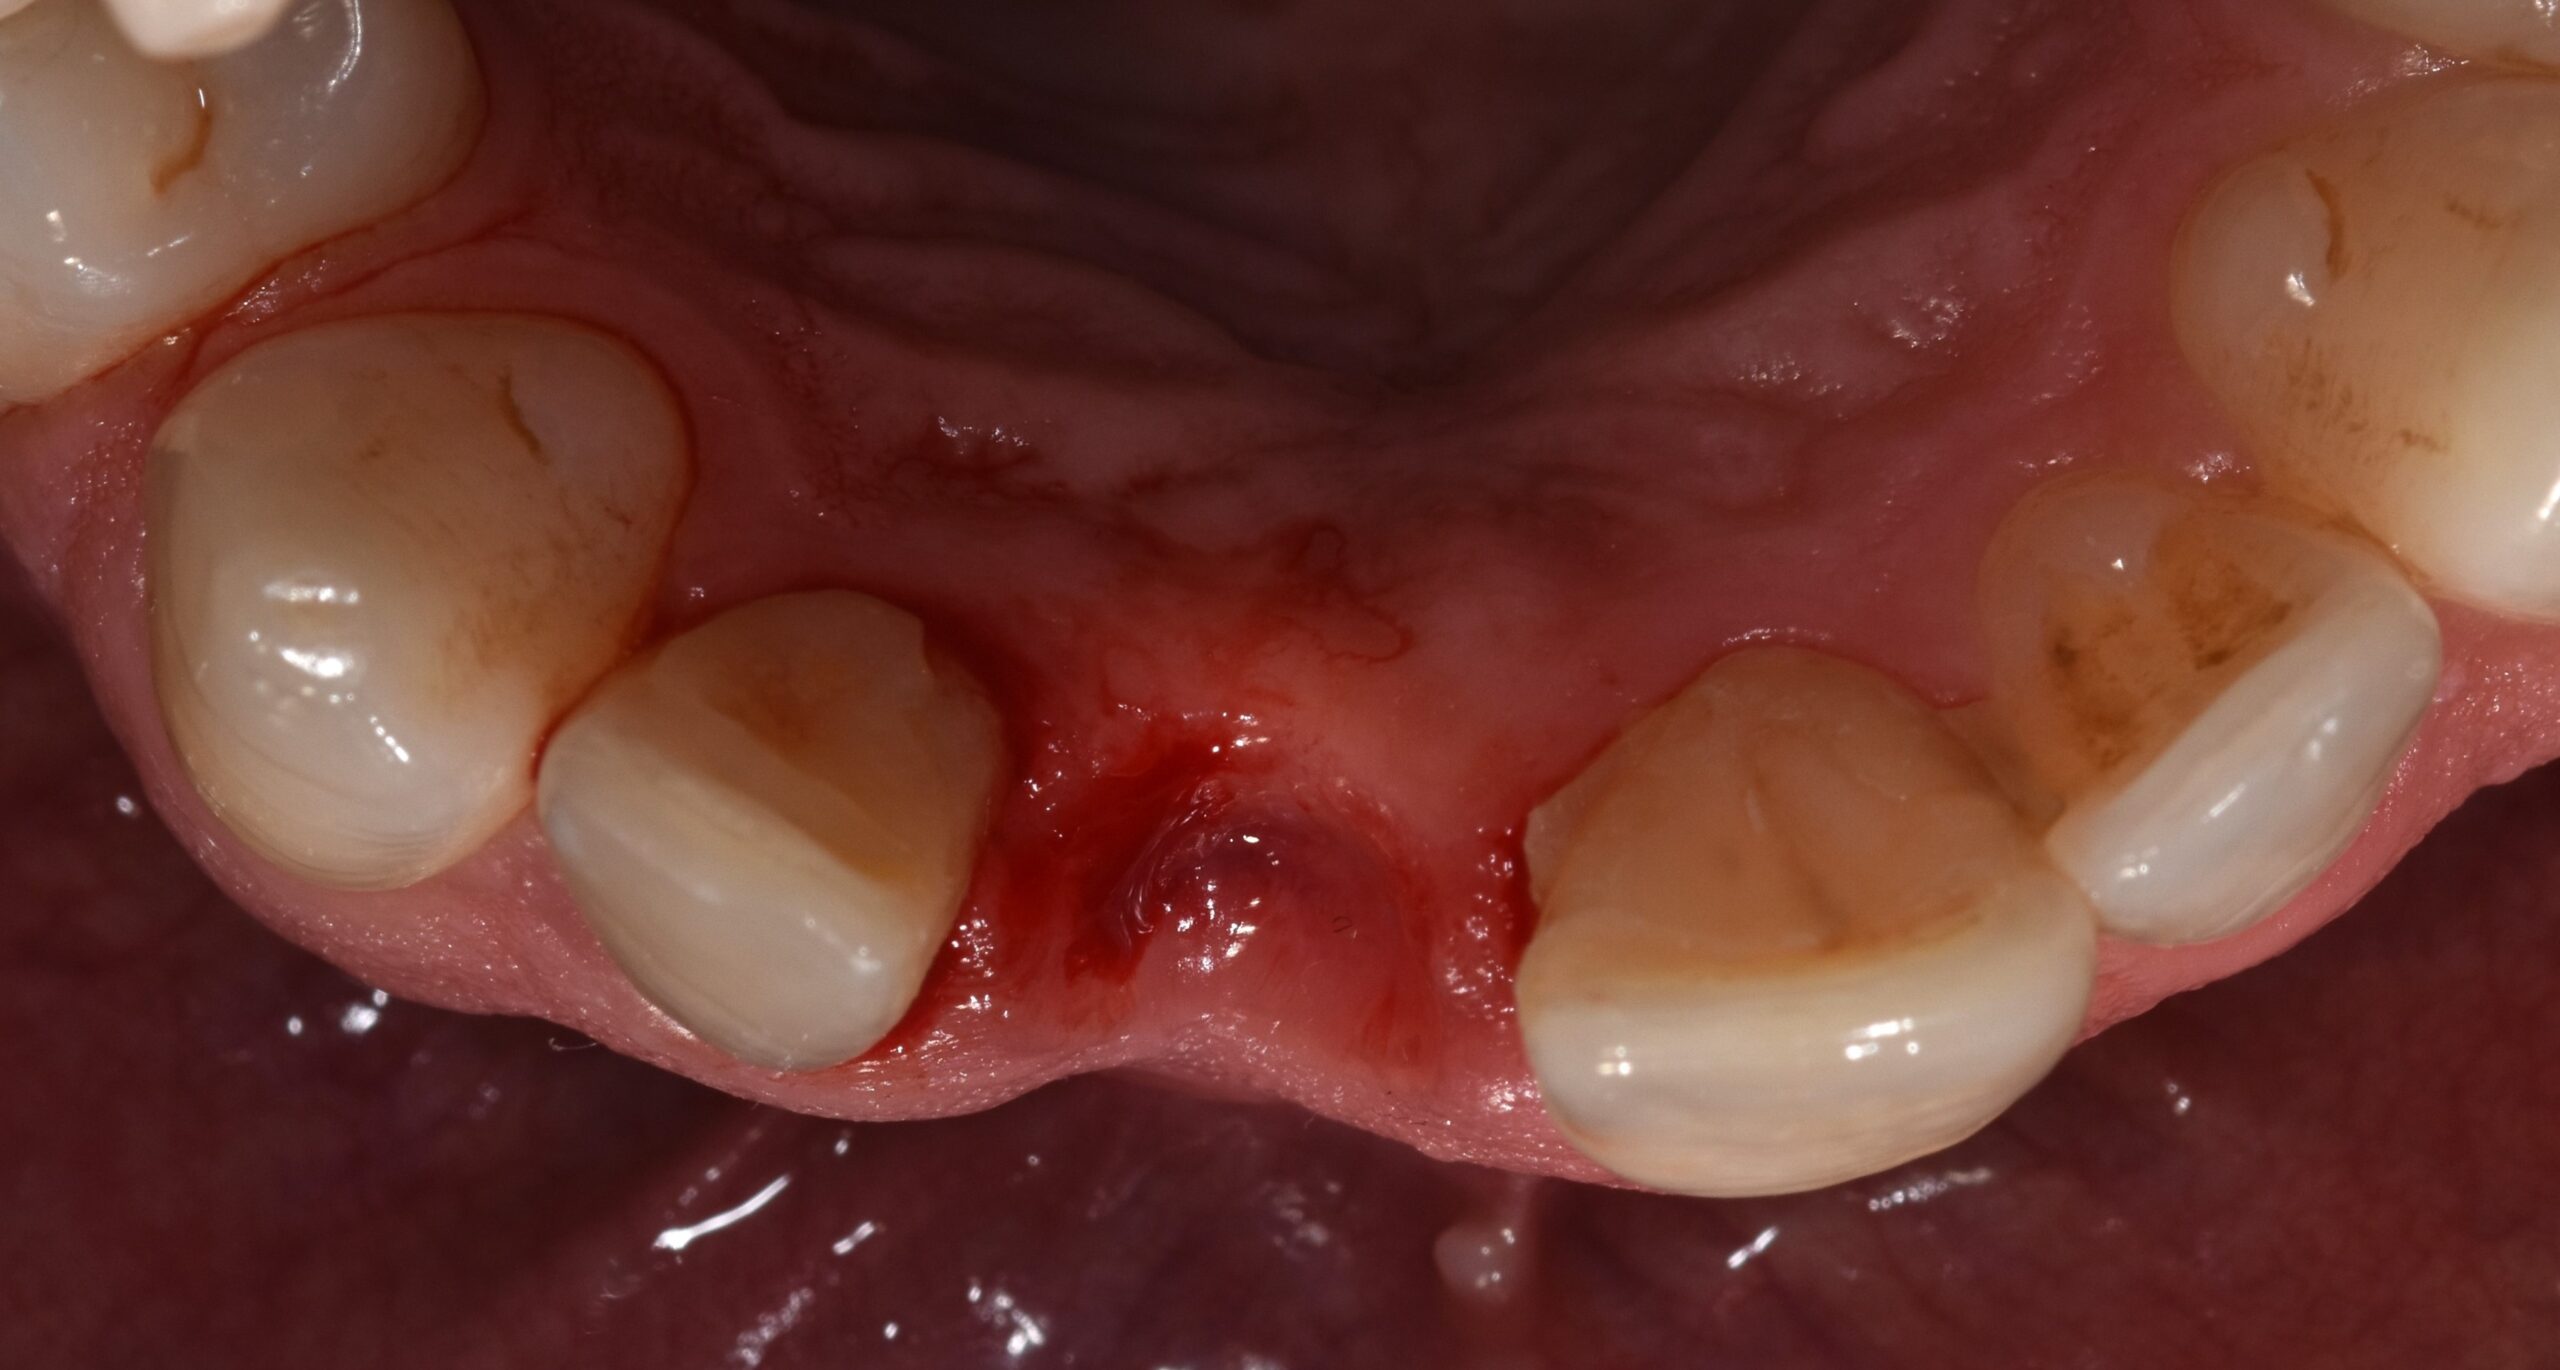

Previa impronta ottica, veniva preparato un Maryland provvisorio di adeguata forma (Figura 4) applicato sul gruppo frontale dopo estrazione atraumatica dell’elemento (Figura 5).

Il provvisorio, di forma ovoidale della parte intra-alveolare, sigillava senza compressione l’alveolo, penetrando in esso per circa 3 mm (Figura 6) (14). Prima della sua applicazione, l’alveolo veniva liberato dal tessuto granulomatoso e riempito con spugna di collagene. Nessun innesto veniva applicato nell’alveolo (15).

La tecnica di espansione della cresta ossea (Figure 9-10) veniva scelta per l’osteotomia, con l’intento di compensare una inevitabile contrazione del suo spessore.

La presenza di una corticale vestibolare integra e di spessore adeguato giustifica la scelta di non utilizzare materiali da innesto eterologhi, consentendo una maturazione del coagulo indisturbata verso la formazione di nuovo osso.

L’inserimento dell’impianto con tecnica espansiva consentiva una compensazione della inevitabile contrazione del sito come sopra rimarcato. Dopo l’osteointegrazione, il sito, seppur “border line”, veniva giudicato morfologicamente adeguato e, pertanto, non veniva considerato un eventuale innesto di tessuto connettivo per perfezionamento del suo profilo, finalizzando il caso con la corona avvitata in zirconio-ceramica.